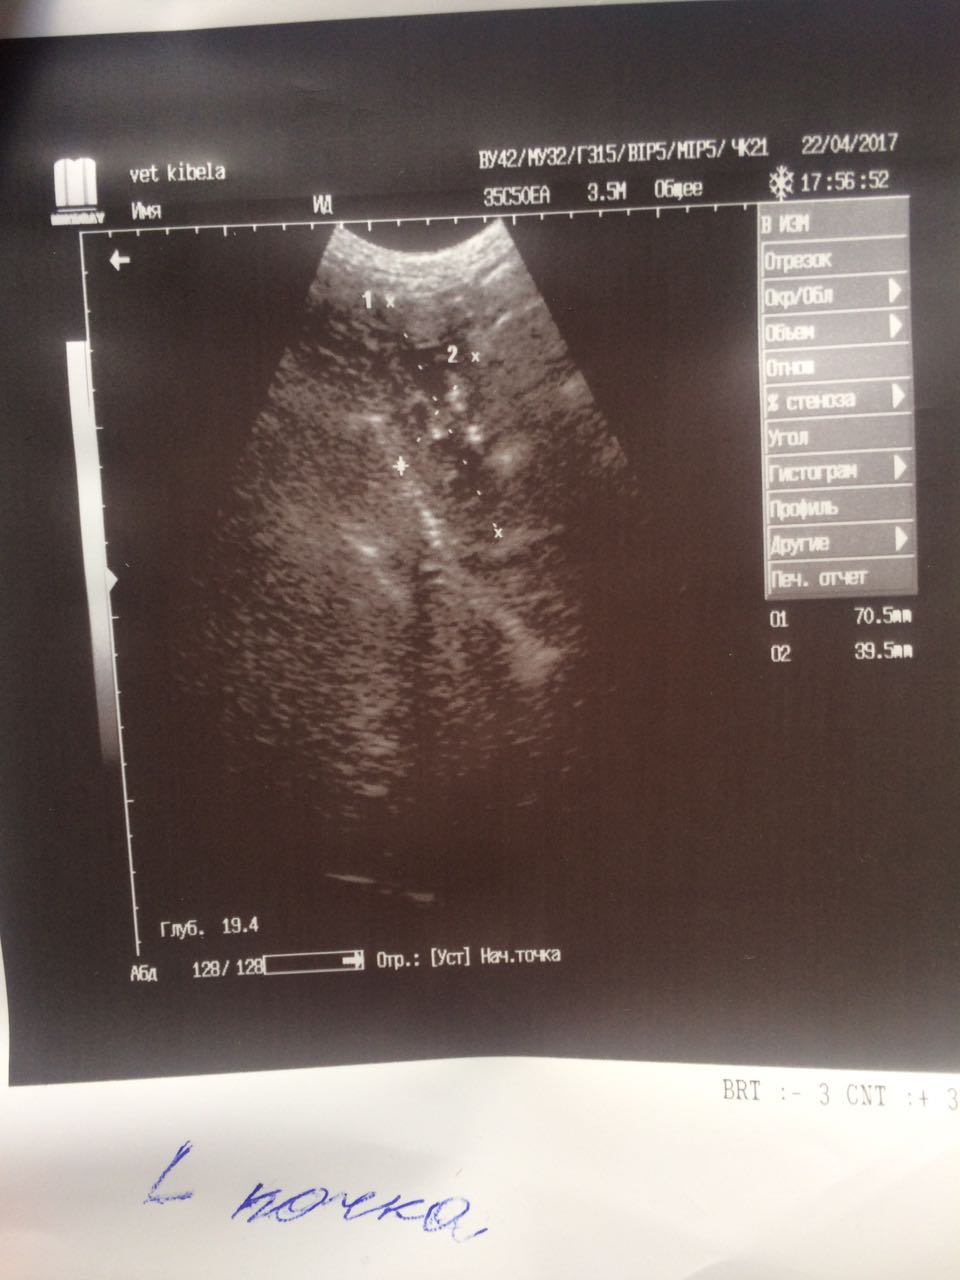

Теперь немного о том что мы нашли на обследование.Не смотря на мои призрачные надежды на доброкачественность образований ,у Лады рак молочной железы. Предположительно похоже на карциному.Конечно хирург сквозь кожу не может разглядеть наверняка ,но полагаясь на опыт может предположить.Из УЗИ мы выяснили ,что пока метастазов в печени,в других органах у нас нет.Есть достаточно большая киста на яичнике и возрастные изменения в почках.